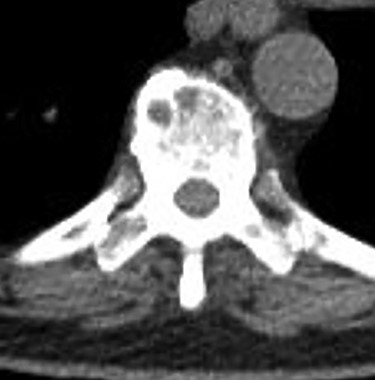

Serum protein electrophoresis confirmed multiple myeloma with two M-spikes (1.6 g/dl and 0.4 g/dl), elevated serum-free kappa concentration (41.5 mg/l) and elevated kappa/lambda ratio (7.41). Peripheral blood smear noted rouleaux formation. Positron emission tomography/CT confirmed bony lesions throughout the axial (Fig. 5) and proximal appendicular skeleton. The patient is currently undergoing chemotherapy with autologous bone marrow transplant.

Positron emission tomography/CT showing numerous foci of uptake involving the axial skeleton (thoracic vertebral and rib lesions noted in this image).